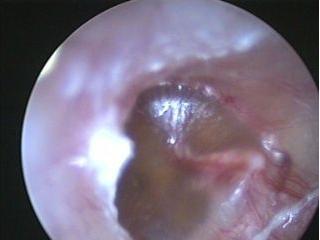

西安新城中大耳鼻喉医院医生表示:用耳内窥镜检查病人的耳部,会发现鼓膜内陷,鼓膜呈淡黄或橙红色,有时透过鼓膜可见气泡。

上图就是一例分泌性中耳炎的鼓膜表现,透过鼓膜可见内有气泡,说明鼓室内有积液